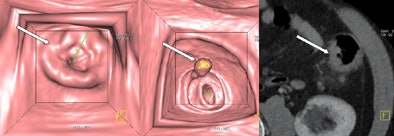

| Images are of a 65-year-old male patient who underwent a single acquisition at dual-source CTC. Above, a stenosing carcinoma was seen in the proximal sigmoid colon in 3D endoluminal views (left, middle) and 2D view (right). Below, an 18-mm colorectal adenoma was also found in the proximal sigmoid colon, and also appears to be enhancing. Bottom image shows an enhancing liver metastasis in the same patient. Virtual unenhanced (grayscale) images are created by electronically subtracting the contrast media. All images courtesy of Dr. Anno Graser. |

The technique is ideal for examining the entire colon in patients with a stenosing colorectal cancer lesion, providing additional insight into the region proximal to the stenosing cancer as well, he said.